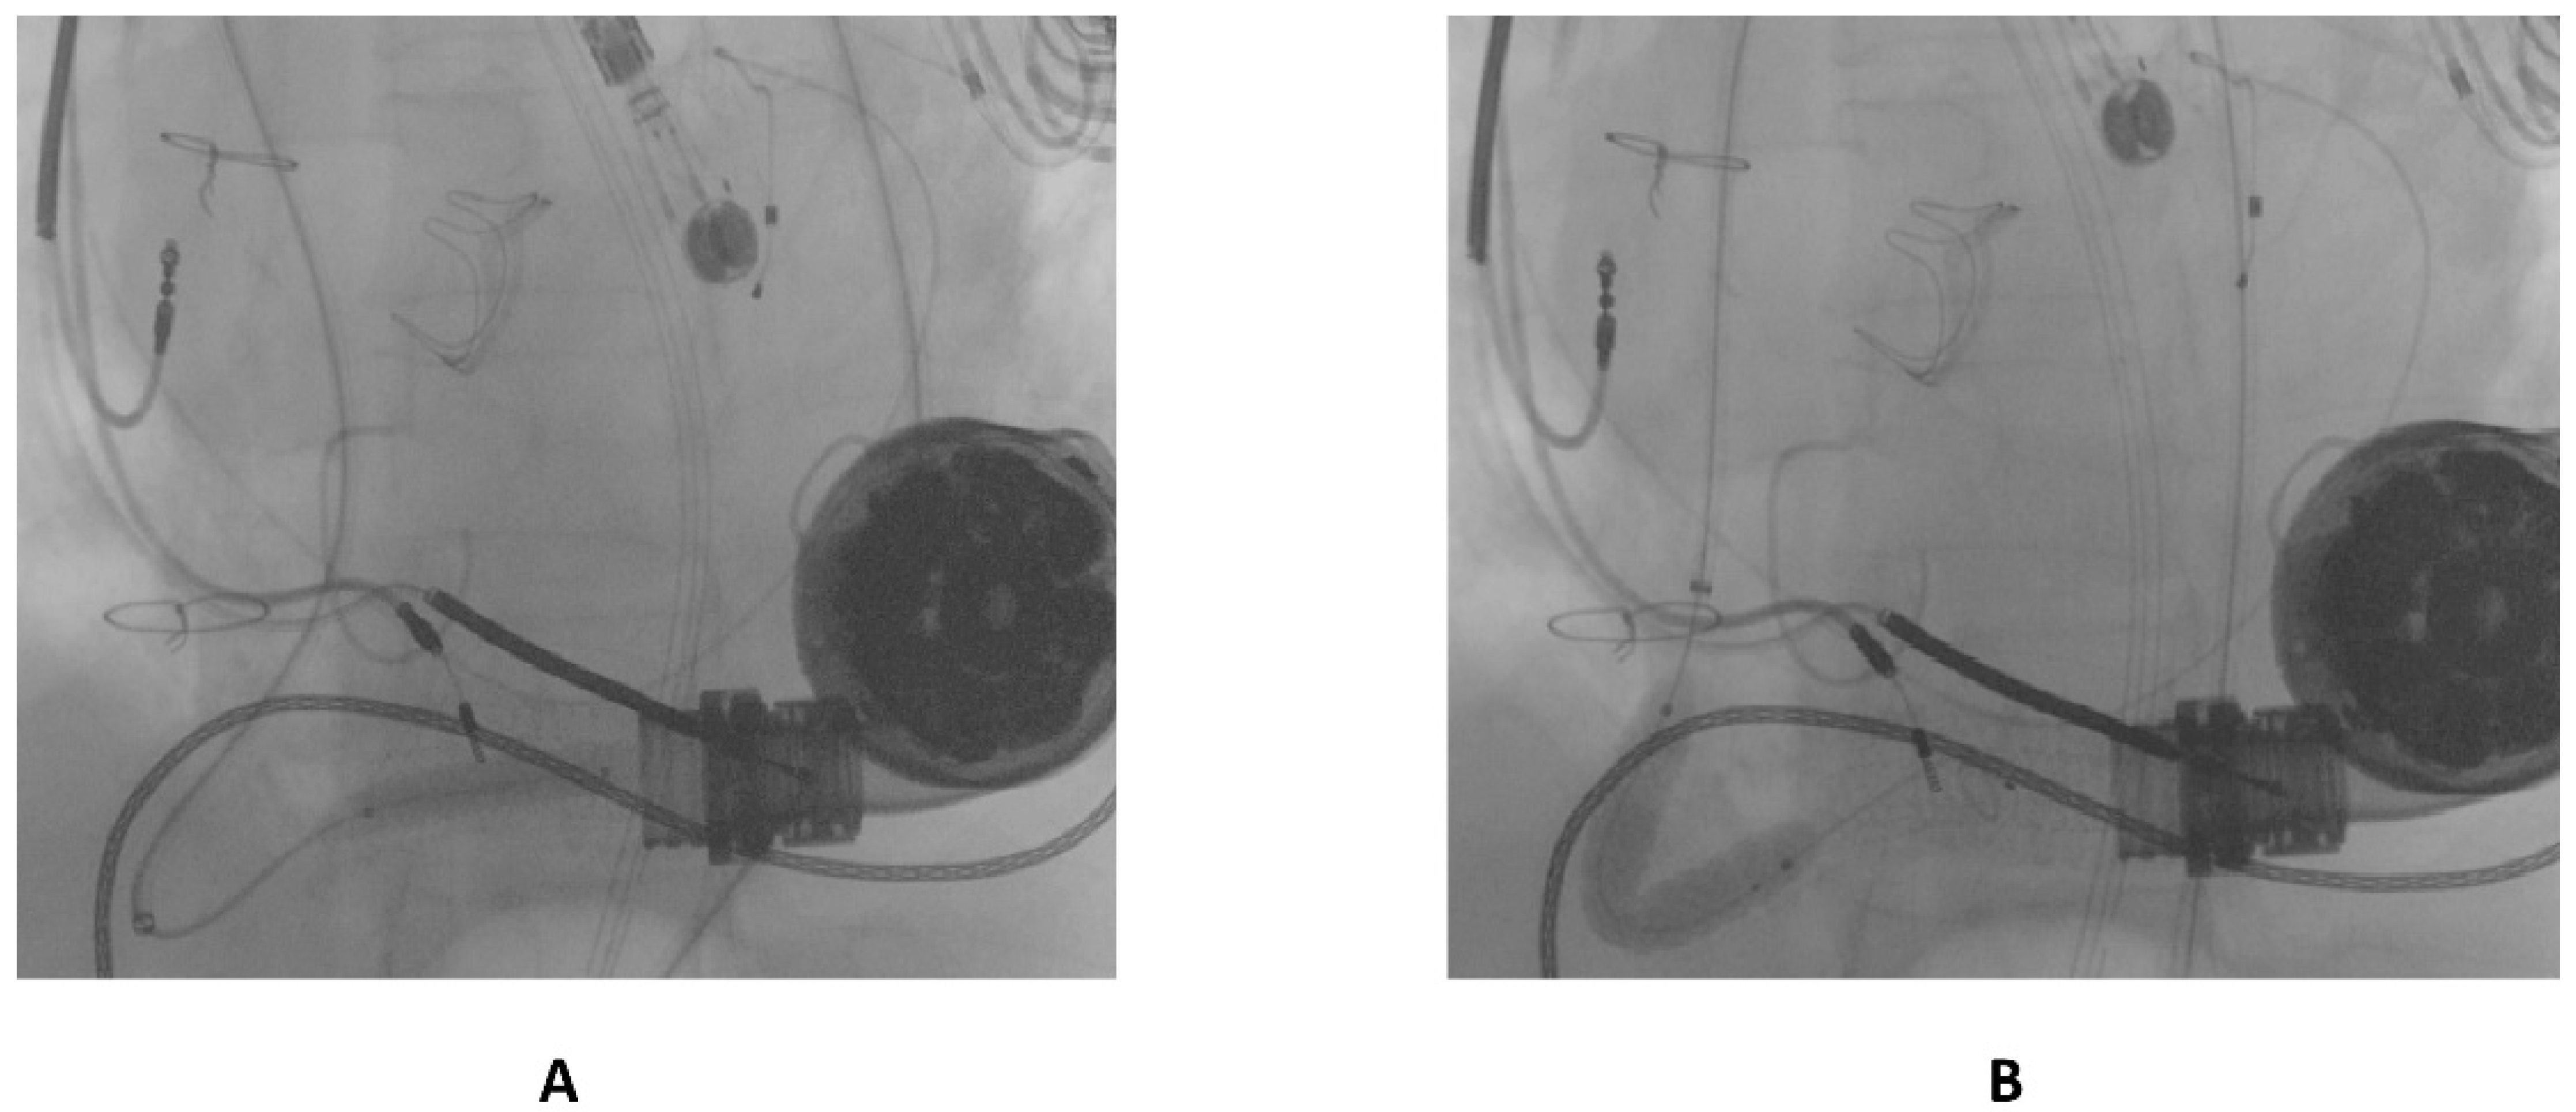

The first guidewire was removed and a 0.035″ × 260 cm stiff guidewire (Amplatz Super Stiff™, Boston Scientific, Natick, MA, USA) was deployed distally. Following this, an “anchoring technique” [8] with a 12 mm balloon located in the proximal tract of the outflow graft was adopted in order to advance the long sheet throughout the kinking. After that, a balloon-expandable 10 × 79 mm endoprosthesis (GORE® Viabahn® VBX) was implanted. Distal anchoring and stent positioning are shown in Figure 3A,B.

Figure 3.

(A) distal anchoring; (B) stent deployment.

Due to severe underexpansion of the implanted stent, several postdilations were performed using peripheral balloons of increasing diameters (MUSTANGTM 0.035″, Boston Scientific) (see Figure 4).

Figure 4.

Postdilation of the implanted stent.